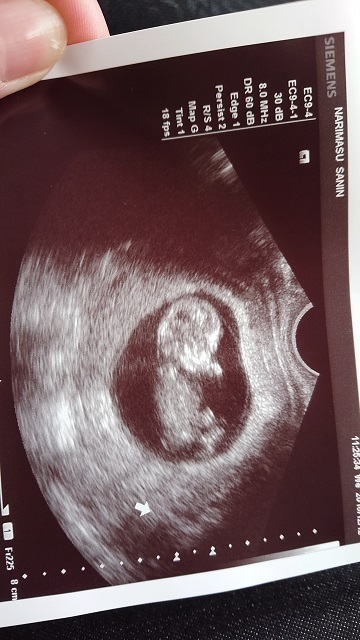

11週0日(11w0d・女の子)|pon2019610 さん(28歳)

エコー写真撮影時のエピソード:

妊娠が分かった産婦人科ではお産ができないため、紹介された産院で初めてのエコーでした。

前回も前々回も流産しており、不安な気持ちいっぱいで産院に向かってしてもらったエコー。

私の不安をよそに、まるで私を安心させるようにいっぱい動いてくれた赤ちゃん。エコーをする先生も笑っておられました。

あまりに動き回るものだから写真におさめるタイミングも大変だったみたいで、いただいた写真を改めて見返すと、きっとぶれてしまったんだと思いますが、まるでくちばしがはえているかのように見える写真が!

おもわず主人と笑ってしまいました(笑)

私の家族に見せると、くちばしあるやん!くちばしっち(たまごっちのキャラ)や!と(笑)

おかげでそのときからお腹の子は『くっちー』と呼ばれています(笑)

産まれてからも私の家族からの呼び名がくっちーのままだったらどうしよう?と今から心配です(笑)